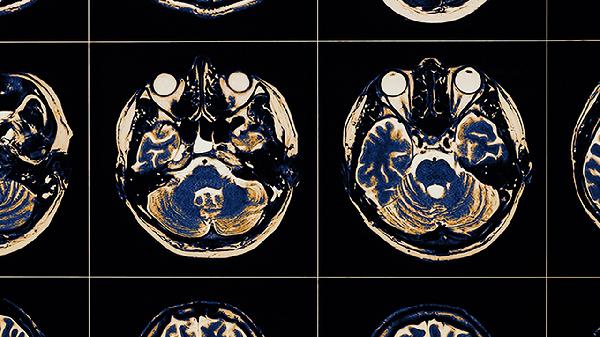

腦血栓形成的原因

腦血栓形成的原因主要有血管內(nèi)皮損傷、血液成分改變、血流動力學異常、動脈粥樣硬化、心臟疾病等。腦血栓通常表現(xiàn)為肢體無力、言語不清、頭暈等癥狀,需及時就醫(yī)干預。